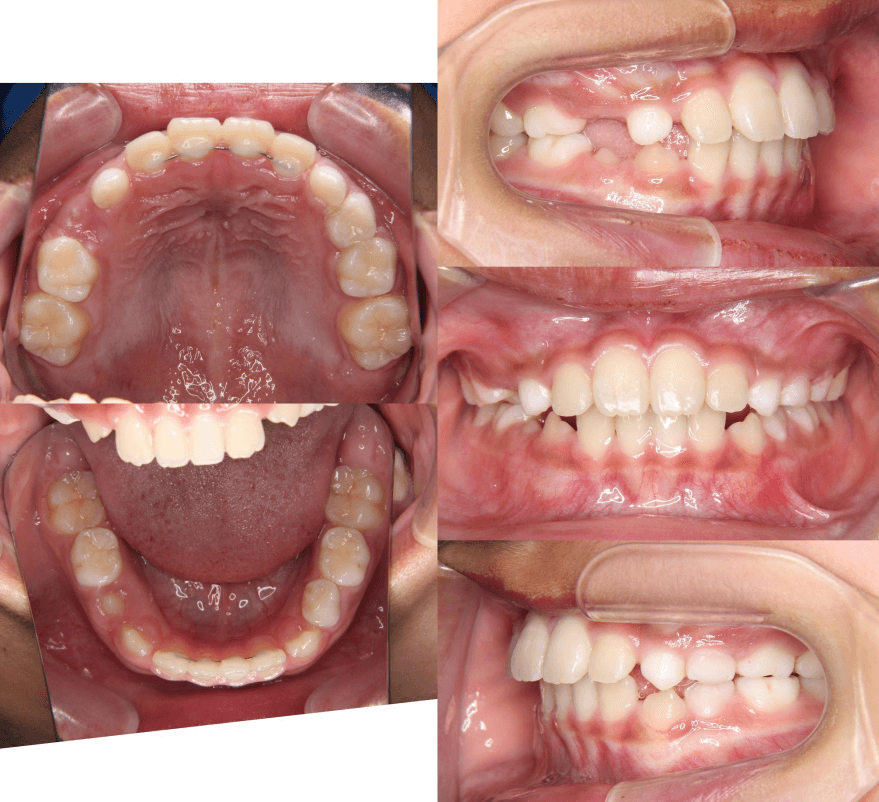

| 年齢・性別 | 8歳9ヶ月の男児 |

|---|---|

| 主訴 | 前歯の咬み合わせが逆になっており、歯根や歯肉への影響を懸念されて来院された患者様です。 |

| 治療期間・回数 | 3年7ヶ月・20回 |

| 費用 | 460,000円(税別) |